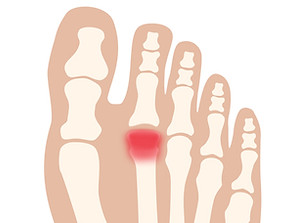

中足痛(症)/Metatarsalgia

中足痛/Metatarsalgia

​足趾の付け根部分に痛みや炎症が生じている状態です。ランニングやジャンプを伴う運動のほか、足の骨格の変形や合わない靴(きつすぎる、またはゆるすぎる靴)も原因になります。

中足痛(症)には、いくつかの日本語訳があり、「中足骨痛症」「中足骨頭部痛」「中足骨骨頭部痛」などと呼ばれることもありますが、日本足の外科学会の用語集では「中足痛(症)」とされています。